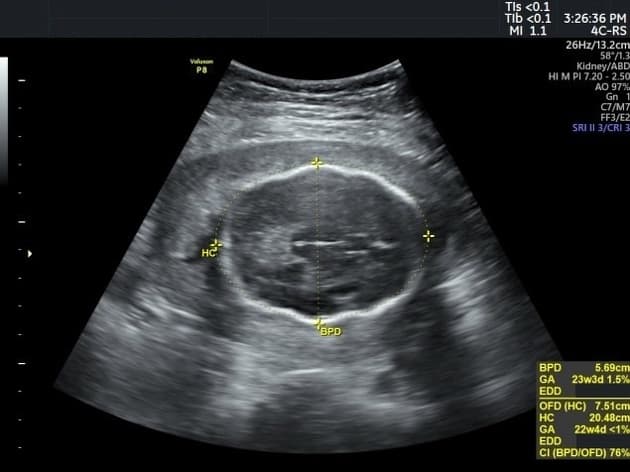

tuổi thai ≤6,2 tuần (chiều dài đầu mông ≤4 mm)

tuổi thai 6,3–7,0 tuần (chiều dài đầu mông 5–9 mm)